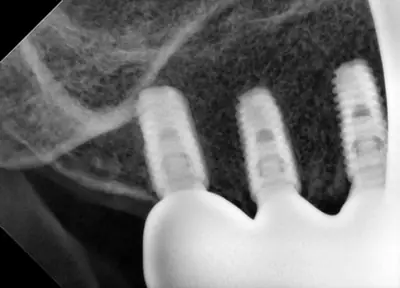

치과 치료를 두려워하는 분들을 위해, 진정요법을 활용한 사례를 소개합니다. 부산에 거주하던 60대 여성 환자가 치아가 많이 손상되어 임플란트와 브릿지 치료를 받았는데, 병원 트라우마와 공포로 어려움이 있었어요. 의식하 진정요법을 통해 깊은 낮잠 같은 상태에서 안전하게 치료를 받았고, 수술 과정도 성공적이었어요. 이 방법은 전신마취보다 안전하고, 환자도 큰 두려움 없이 치료를 마칠 수 있어요. 치과 공포증이 심한 분들도 전문가와 상담 후 진정요법을 고려해보시면 좋겠습니다.